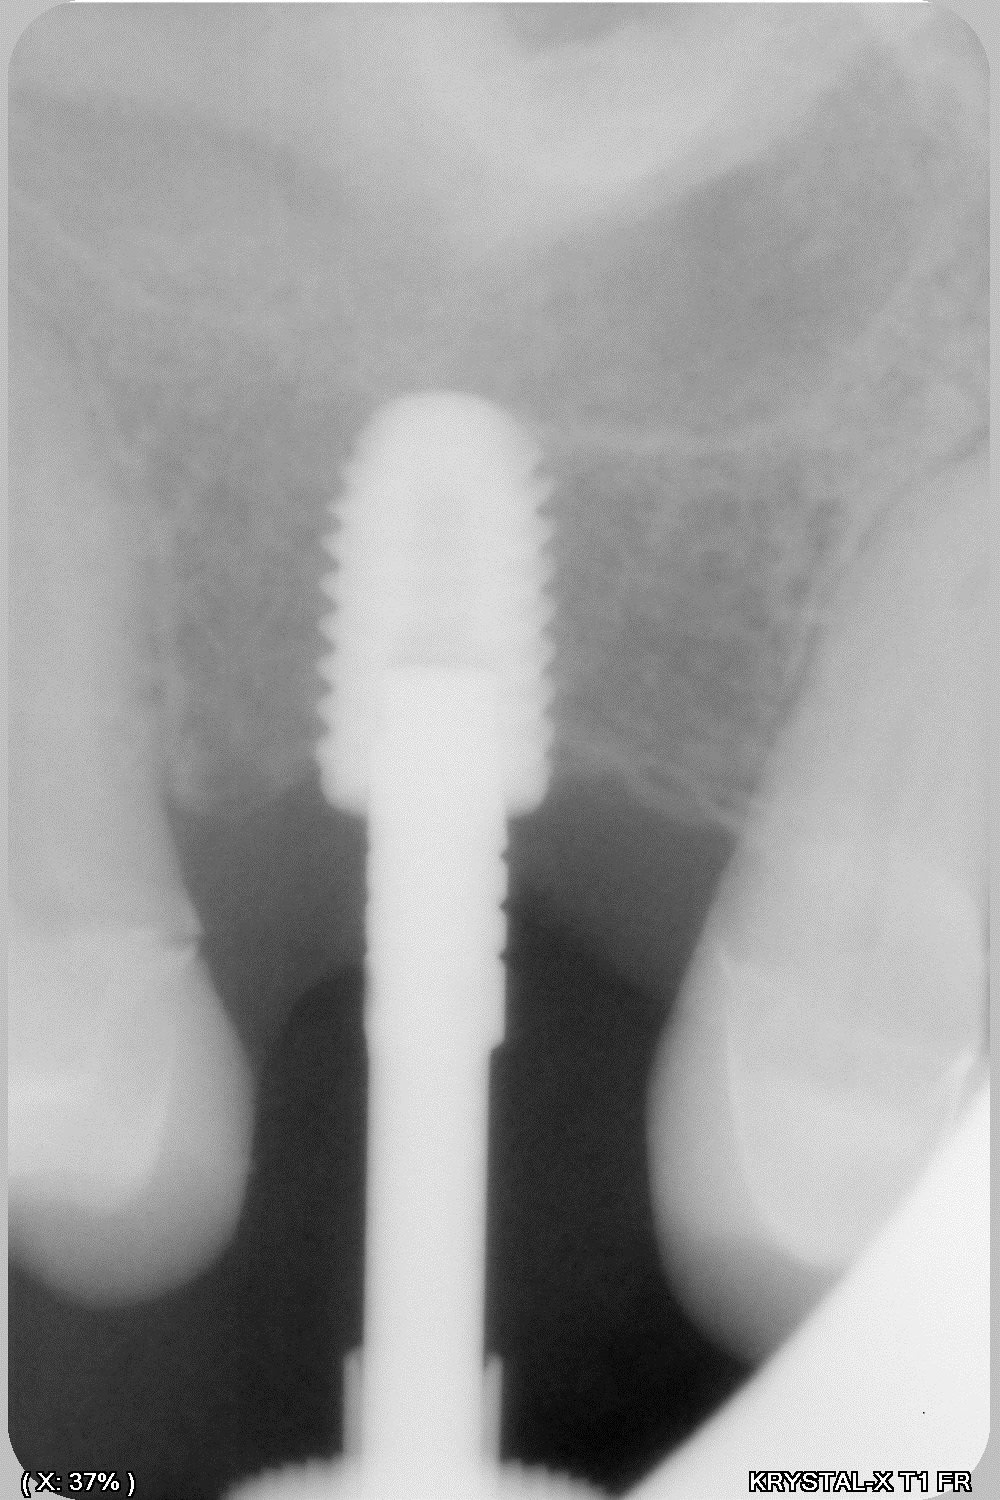

14/01/2020 à 13h00

donc tu avais raison Enlaye... le bridge à cassé (sur un carambar quand même:-))

dépose, nettoyage sablage des couronnes récupérable et pose d' implant, uniquement en manuel (os tendre)

029 lbedjl - Eugenol

030 l2v2ab - Eugenol

031 eprqqn - Eugenol

032 ar3ton - Eugenol

033 bghvnq - Eugenol

039 xjmgt2 - Eugenol

041 yfawnc - Eugenol